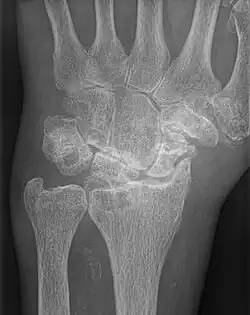

| AP wrist x-ray demonstrating Stage III scapholunate advanced collapse | |

Stage III

Stage III SLAC wrist involves the entire radioscaphoid joint and the capitolunate joint.[3] The PA wrist x-ray will demonstrate sclerosis and joint space narrowing between the lunate and capitate. Over time, the capitate will migrate proximally into the space created by the scapholunate dissociation.[2] The radiographic findings in Stage III SLAC wrist are synonymous with the Terry-Thomas sign, indicating complete scapholunate dissociation.[2]